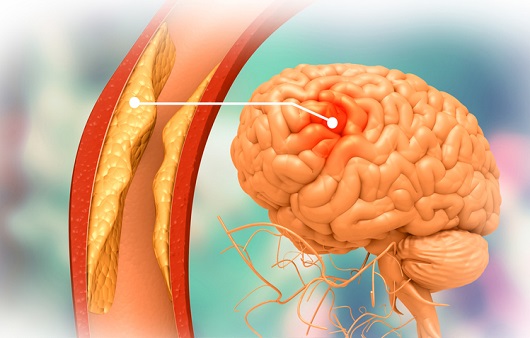

뇌경색 초기증상에 대하므로 살펴볼게요니다. 뇌에도 혈관이 있어서 피가 흐르고 있어요. 뇌에 있는 혈관이 막혀서 뇌의 일부가 손상되는 것을 뇌경색이라고 말해요. 뇌혈관이 막혀 뇌가 손상되면 장애가 발생할수 도 있으므로 뇌 연관 질환은 각별한 주의가 필요해요.

뇌에 제공되는 혈액량이 줄어들게면 뇌가 수습해야 되는 역할들을 제대로 실행해 낼 수 없게 돼요. 뇌혈류가 연속적으로 감소되면 뇌조직에 괴사가 시작되고 괴사된 뇌조직이 회복 불가능한 상태가 되면 뇌경색이라고 진단을합니다. 그러므로 뇌경색 초기증상을 알아두고 방지해억제해하시는게 중요해요.

뇌경색의 주된 이유가 되는 것은 혈전이지요. 혈전이란 혈관 속에 피가 굳어진 덩어리를 얘기하는데 이것이 혈관을 막는 것이 뇌경색에 큰 영향을 줄 수 있습니다. 평균적으로 많이 발생하는 연령대는 5~60대이지요. 뇌경색은 양쪽 뇌에 모두 나타나는는 것이 아니라 주로 한쪽 뇌에만 발생하지만, 주로 한쪽 팔다리가 마비되었다거나 얼굴 근육이 굳어버리기도 해요. 그렇기에 뇌경색 초기증상이 발생한다면 민첩하게 대응를 해야 하겠습니다.

또 뇌경색의 까닭은 혈관의 협착을 유발시키는 동맥경화증이고요. 동양에서는 뇌내동맥경화증이, 서양에서는 경동맥동맥경화증이 많이 나타나고다. 그리고 흡연, 고지혈증, 당뇨병, 고혈압, 건강에 옳지 않은 식습관, 스트레스 등도 뇌경색을 발생시키는 위험요인입니다.모든 질병에 단일 이유가 되는 것이 없듯이 뇌경색도 단일 이유가 되는 것이 아닐 수 있고요.